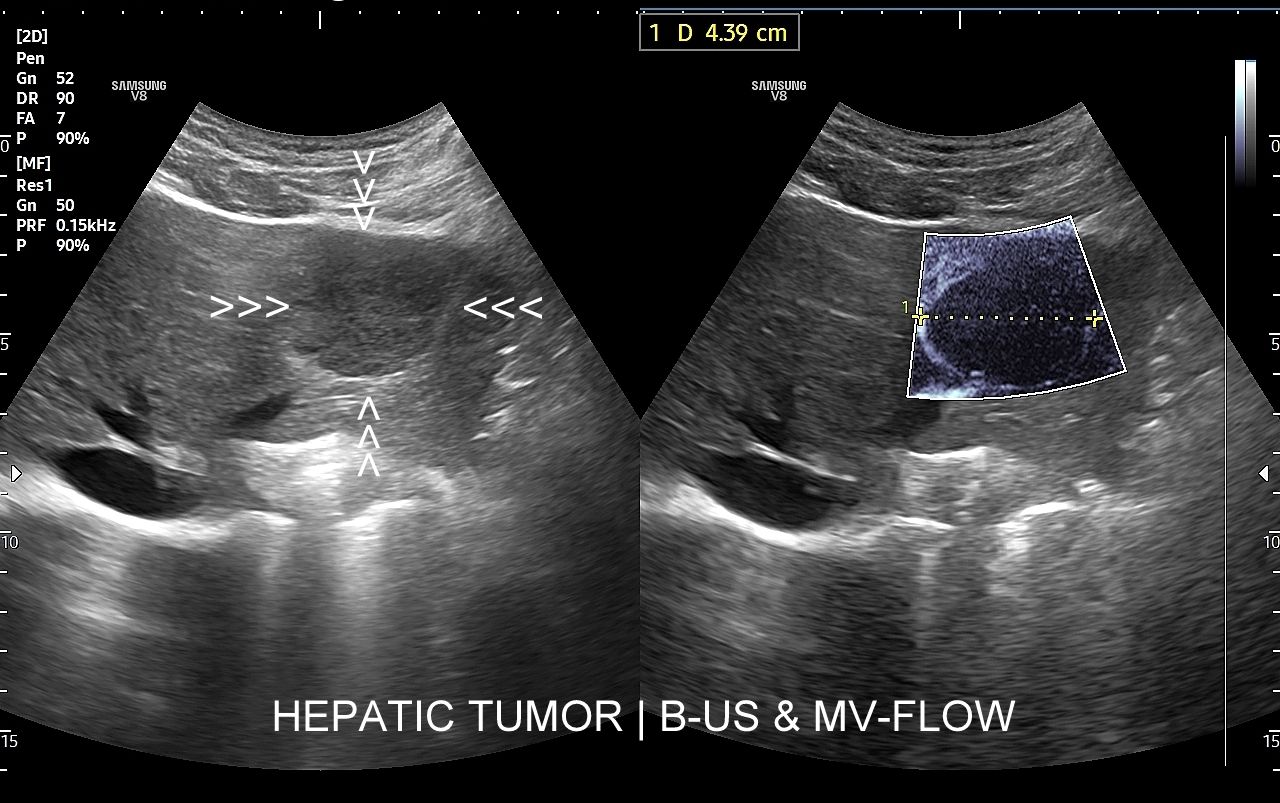

Badanie USG z kontrastem najczęściej wykorzystuje się do oceny zmian ogniskowych w wątrobie, potocznie nazywanych guzami wątroby, z których wiele ma na tyle specyficzny obraz mikrounaczynienia w obrazowaniu CEUS, że możliwe jest uniknięcie konieczności badania obciążającymi metodami TK lub MRI. Badanie CEUS w przeważającej większości pozwala odpowiedzieć, czy zmiana ogniskowa wątroby ma cechy złośliwe czy łagodne. Dodatkowo CEUS jest pomocny do wykrywania przerzutów do wątroby pochodzących z nowotworów w innej lokalizacji. W przypadku przerzutów o wielkości mniejszej niż 1 cm CEUS ma większą czułość aniżeli badanie TK.

CEUS jest badaniem w czasie rzeczywistym pozostającym pod kontrolą operatora, podczas którego możliwe jest wykonanie próby czynnościowej oraz natychmiastowe powtórzenie całego badania w razie konieczności. Możliwości takich nie dają ani TK ani MRI. Dodatkowo CEUS cechuje się o wiele większą rozdzielczością czasową w porównaniu do wspomnianych metod, co umożliwia uwidocznienie wczesnej fazy tętniczej unaczynienia podejrzanej onkologicznie zmiany ogniskowej w wątrobie i jej lepszą charakterystykę.

Narządem, w którego diagnostyce najczęściej wykorzystuje się CEUS, jest wątroba; w dalszej kolejności nerki, trzustka, protezy naczyniowe aorty, drogi żółciowe oraz inne narządy wewnętrzne.